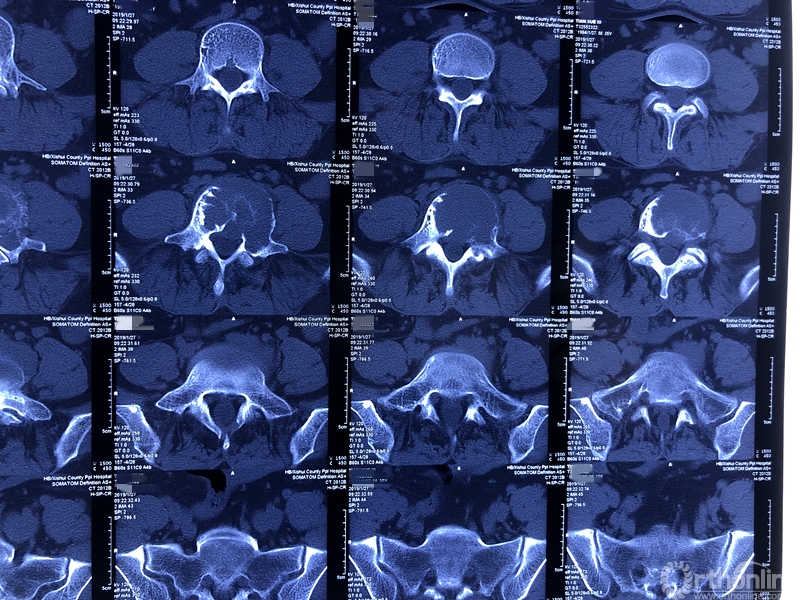

术前CT三维重建